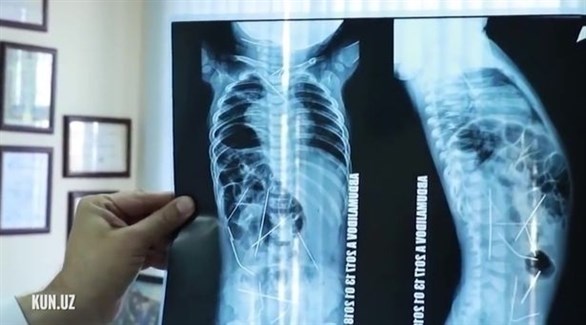

وأظهرت صور الأشعة السينية، وجود 16 إبرة خياطة داخل جسد الطفل، في كل من القلب والعنق والعمود الفقري والقولون والمثانة، وذلك بعد نقله إلى المستشفى، حيث خضع على الفور لعملية جراحية عاجلة استمرت 9 ساعات، تمكن الأطباء فيها من إزالة 13 إبرة.

وخلال العملية الجراحية الدقيقة، أزال الجراحون 3 إبر من صدر الطفل، و9 أخرى من بطنه، وواحده من صدره، ومن المقرر أن يخضع لعملية جراحية أخرى، لإزالة الإبر المتبقية، والتي لا تشكل تهديداً لحياته، بحسب صحيفة ميرور البريطانية.